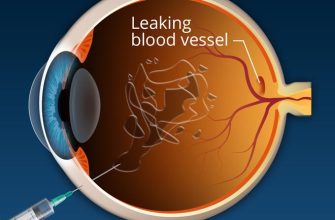

Retinopathy is a condition that affects the retina